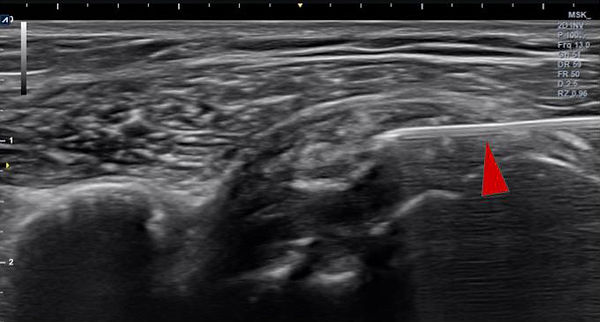

초음파 검사상 발목 내측에 정상적으로 신경과 혈관이 나란히 지나가는데

(그림 5 빨간 선;혈관, 노란 선;신경)

증상이 없는 반대편에 비해 혈관이 비정상적으로 커져있으면서 신경을 자극하는 것을 확인할수 있었다.

초음파 유도하에 혈관에 의해 신경 자극을 줄이기위한 신경 박리 주사를 시행하였다.

환자는 1주 후 내원시 증상이 많이 호전되어 추가로 신경 박리 주사를 시행한 후 증상이 사라졌다.